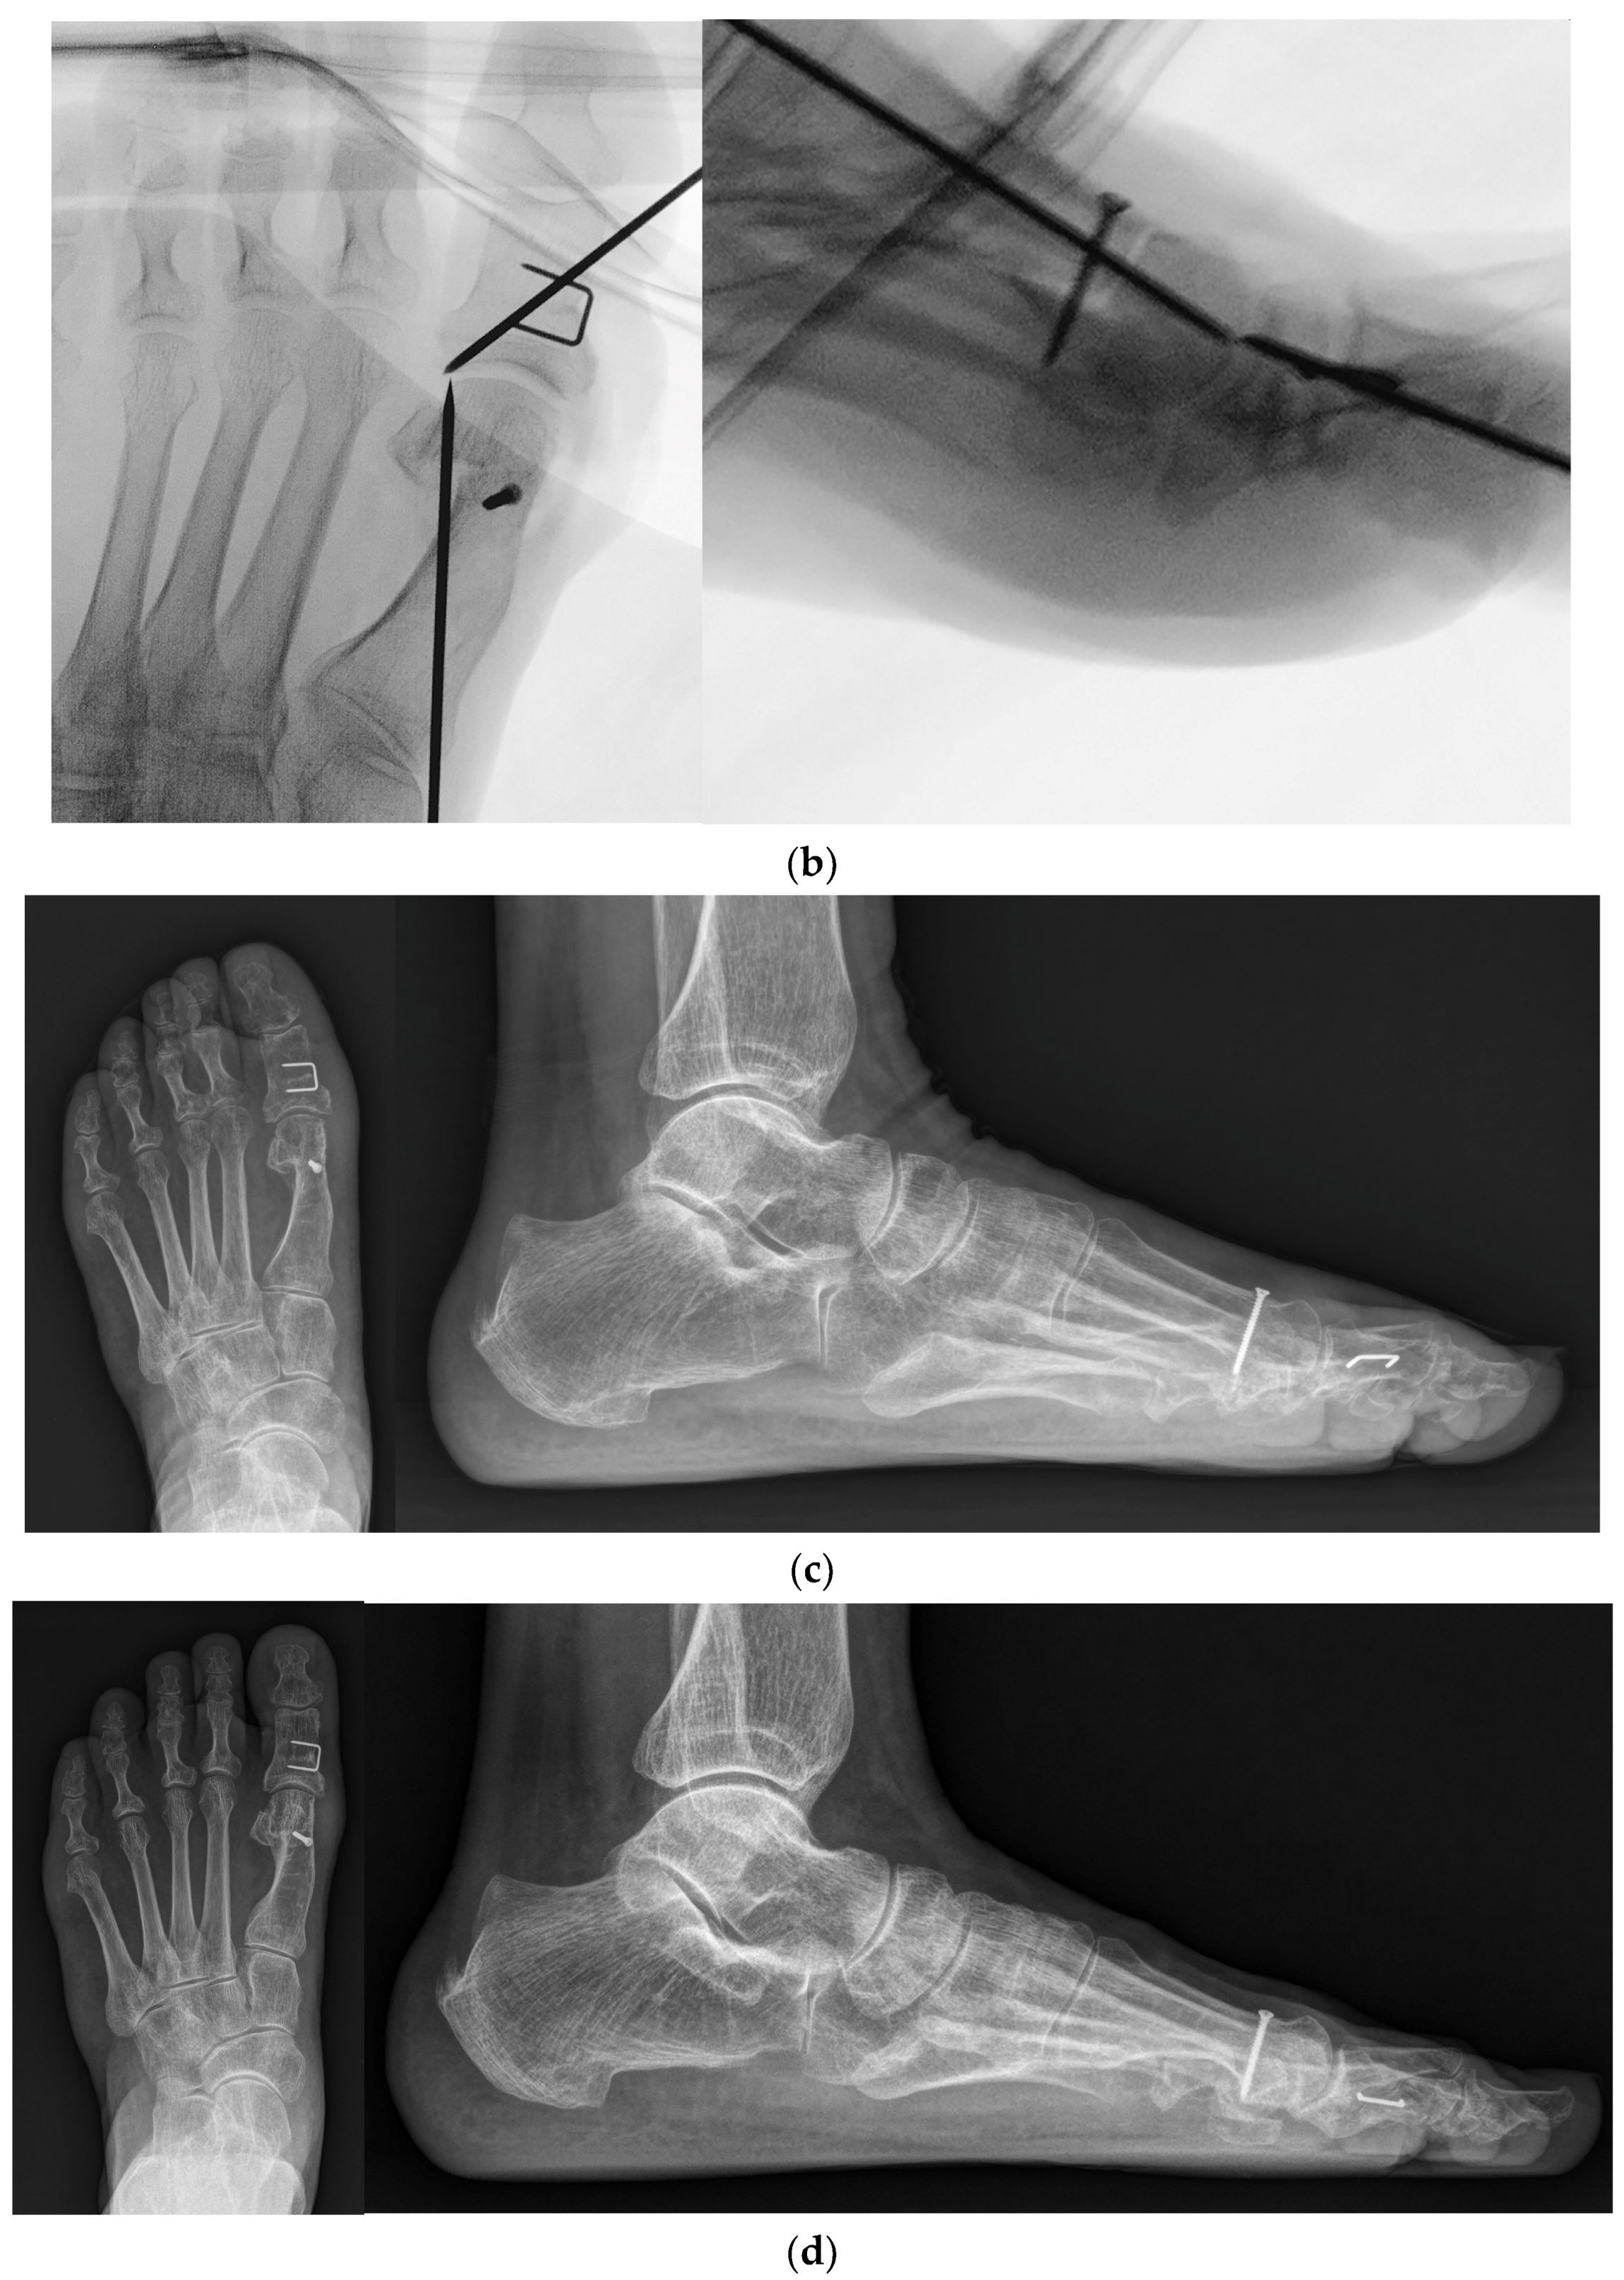

Figure 3.

(a) Preoperative standing foot anteroposterior and lateral radiographs; (b) Intraoperative foot anteroposterior and lateral fluoroscopy images; (c) Standing foot anteroposterior and lateral radiographs at 2 months post operation; (d) Standing foot anteroposterior and lateral radiographs at the final follow-up.

Following the modified 90-degree DCMO, a skin incision was extended distally to the level of the proximal phalanx diaphysis. A medial closing-wedge proximal phalangeal osteotomy, also known as Akin osteotomy, was performed using a saw. A temporary 1.5 mm K-wire was inserted from the distal to proximal directions. After pre-drilling the holes, a 10 mm stainless steel staple (QuickFix Staple System, Arthrex, Inc., Naples, FL, USA) was inserted for the fixation of phalangeal fragments. Intraoperative fluoroscopy was performed to ensure an appropriate length of the cortical screw, a proper location of the staple, and non-invasion of the MTP joint by the temporary K-wires (Figure 3b). In addition, Weil osteotomy was performed in other lesser toes, if needed.

Rehabilitation protocols were as follows: (1) At 2 weeks post operation, patients were advised to make an outpatient visit for the removal of the skin suture and temporary K-wires. Taping was applied to maintain the position of the hallux. Patients were allowed partial weight-bearing with the heel using crutches. (2) At 4 weeks post operation, patients were advised to remove the taping and splint. However, a postoperative shoe brace with a soft hallux valgus brace was worn for another month. (3) At 2 months post operation, the patients were instructed to sustain activities of daily living with a full weight-bearing and wear their own shoes (Figure 3c). Figure 3d shows the radiograph obtained at the final follow-up.